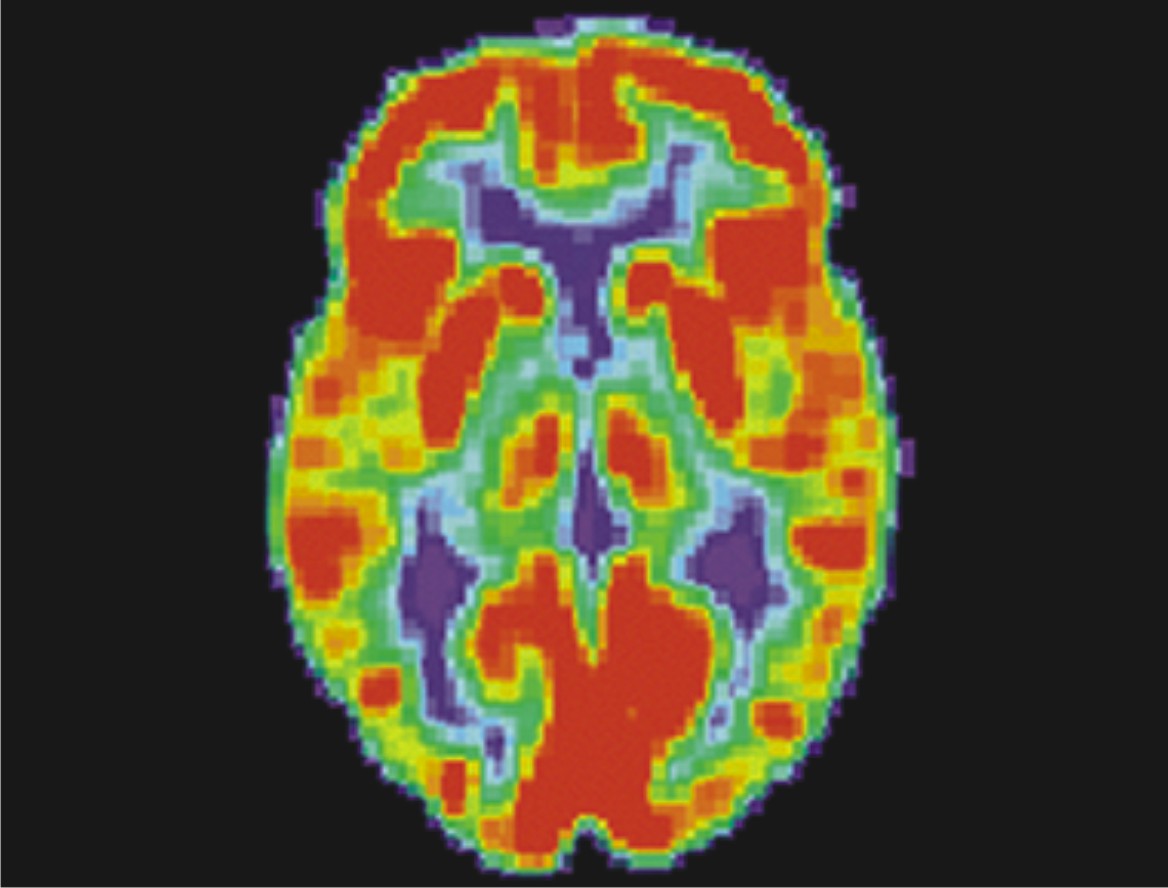

法国人赫尔维·普拉特尔和让-克劳德·巴龙则采用正电子发射断层扫描(PET)来检验人脑对音乐的反应,他们给受试者听的是大众耳熟能详的比如《蓝色多瑙河》之类的音乐,结果发现除了能够激发颞叶的活动之外,位于大脑背面的视觉皮层也亮了起来。这一结果无疑在提醒科学家们,音乐是一个综合功能,它牵动了进化中得来的种种能力。

现代神经科学的发展已经证实,丰富多彩的音乐影响到了人脑中的许多区域,主要包括如下一些——

1.前额叶皮层:这个大脑区域扮演着一个与创造力、满意度以及暴力冲动有关的角色,当一个节拍消失的时候,它会出现反应。最近有个研究还表明,在即兴表演中,前额叶皮层中与表演控制相关的部分会关闭,同时另一个自发意识的部分会被启动。

2.运动皮层:音乐和运动不可能分割,闻歌起舞,而演奏乐器更需要良好的生理运动来配合。

3.感觉皮质:演奏乐器时的动作会给感觉皮层输送一个策略信号。

4.听觉皮层:听到任何声音都会激发本区域,其中包含对音高和基调的分析。

5.视觉皮层:看乐谱或观看表演者的动作能激活视觉皮层。

6.小脑:小脑被认为是掌管肢体运动的,因为那些让人忍不住想用脚打拍子及手舞足蹈的音乐不可能不撩拨到它,它也参与了情感方面的活动,并能分辨出大小和弦的不同。

7.海马:这是一个和长期记忆有关的大脑区域,或许能够帮助大脑找回记忆并为声音提供一个“上下文背景”,当音乐出现情绪性变化时它会被激活。

8.杏仁核:它似乎参与了与音乐有关的记忆,在大和弦及小和弦上的反应有所不同,而那种听音乐时到了某个转换部分人会突然一颤的反应也是因为它被唤醒了。